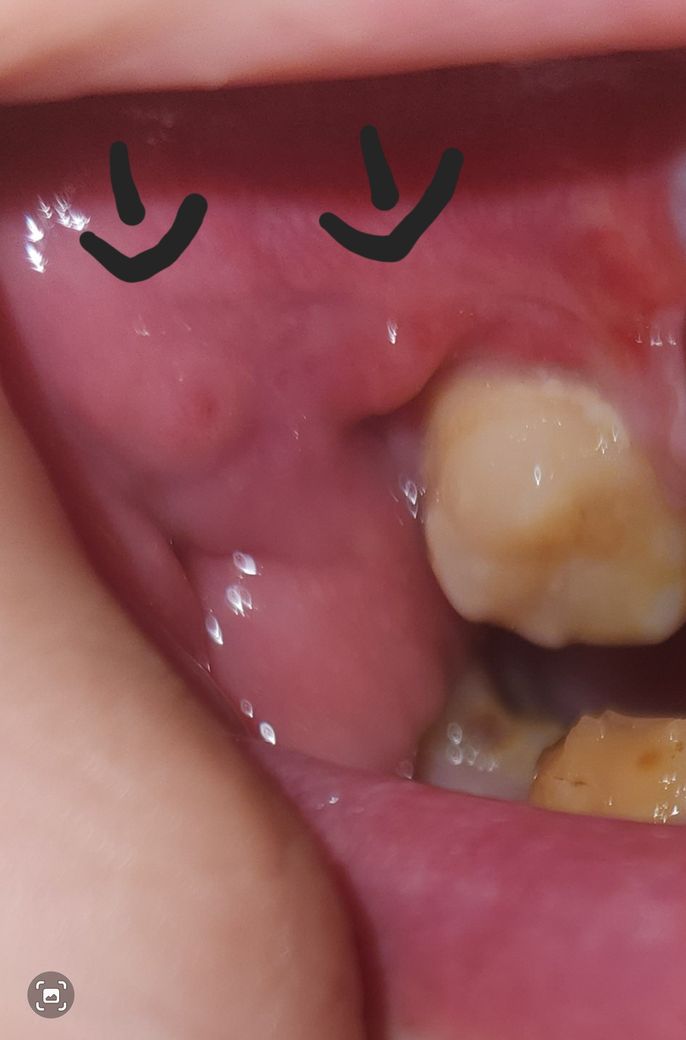

잇몸에 혹 생겼는데 괜찮을까요~???

잇몸에 혹? 비슷한게 생겼는데 혹시 괜찮나 싶어서요

구강내의 단순 연조직이 증식된것일수도 있고 염증에 의한 것일수도 있습니다.

크게 문제가 잇는건 아니고 잇몸이 낫는 과정에서 잇몸이 약간 과증식되서 그런거니 너무 걱정하지 않으셔도 됩니다.

우선 이 혹이 통증도 없는 경우 우선 지켜보길 권하며, 만약 통증이 수반되는 경우 잇몸농양일 가능성이 많습니다.